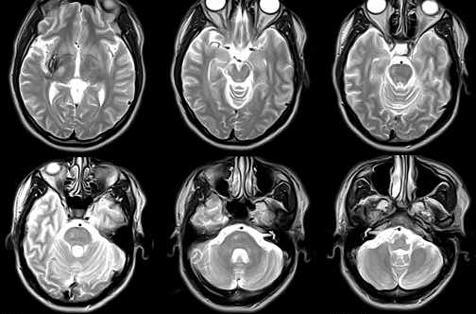

Estes dados implicam que o mergulho pode produzir danos subclínicos ao cérebro, medula espinhal (Fig. 2, 3), ouvido interno, retina e pequenas vias aéreas do pulmão. Outros estudos sugerem diminuição significativa das funções pulmonares e cognitivas.

A ressonância magnética (MRI) deu aos investigadores uma ferramenta adicional para estudar o sistema nervoso central em mergulhadores. Com a ressonância magnética, foi relatada alta intensidade de sinal (pontos brilhantes), indicando danos nos tecidos, em mergulhadores e acredita-se que tenha grande potencial para identificar danos causados ao SNC.

Foi usado pela primeira vez pelos noruegueses (Todnem e associados) para estudar doenças descompressivas, e eles descobriram que até 33% de todos os mergulhadores apresentavam alterações de alta intensidade de sinal. Estudos semelhantes realizados por Brubakk e Rinck e colaboradores confirmaram essas descobertas.